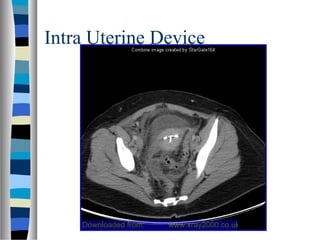

Intra Uterine Device